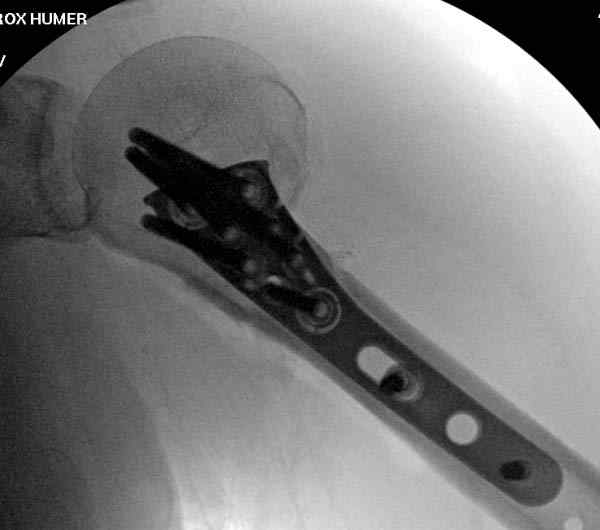

Здесь пример открытой репозиции 57 летнего с переломом плеча (1,2)  смещение обнаружено на  интероперационном снимке. При нормальной прямой проекция (3) угловое смещение обнаружили в аксиальной проекции (4)

После устранения смещения пластина установлена выше (5,6,7) и финальные снимки (8,9,10)